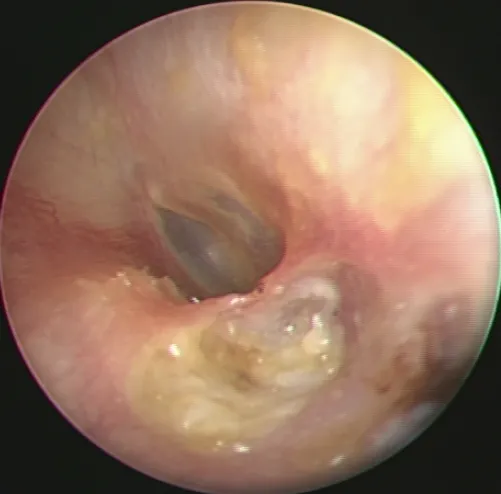

這題的解題核心在於辨識內視鏡下咽喉部的典型白色斑塊病灶,並結合病人的高風險因子(糖尿病、吸入式類固醇使用)來判斷最可能的感染。圖片中可見咽喉黏膜上有多處白色、像乳酪狀的斑塊,這是念珠菌感染的經典表現。

這張耳鏡影像顯示外耳道內有白色、像乳酪狀的堆積物,並且侵蝕了耳道骨壁,這是典型的耳道膽脂瘤(ear canal cholesteatoma)表現。